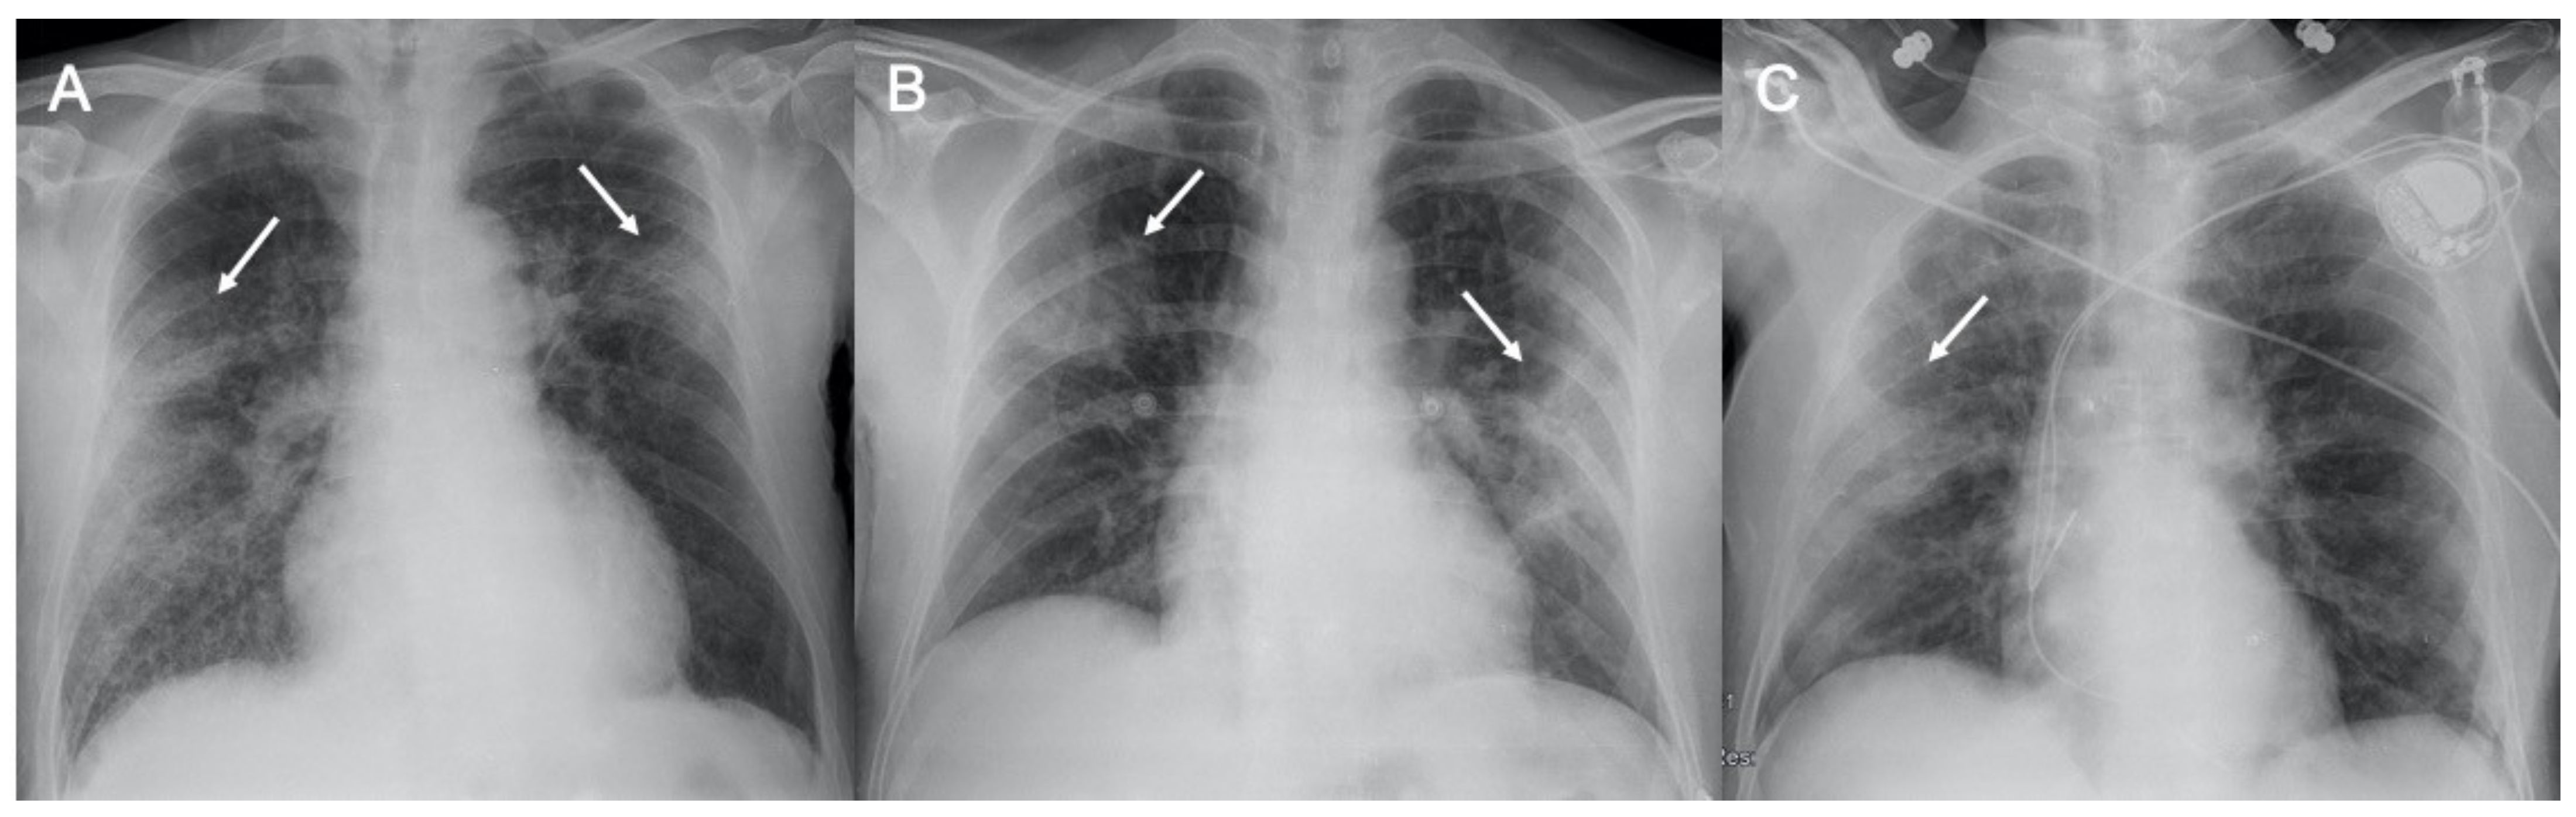

• 常見病毒性肺炎的影像學特征︱圖文并茂

常見病毒性肺炎的影像學特征︱圖文并茂

醫脈通編譯整理,未經授權請勿轉載。病毒性肺炎是常見的呼吸道疾病之一,其風險因素有很多如免疫系統紊亂、兒童營養不良、吸煙和慢性阻塞性肺病等,尤其免疫低下的人群具有高感染風險。病毒感染的臨床病程與宿主的免疫狀態有關,其癥狀具有非特異性,如咳嗽、發熱和呼吸困難,難以進行鑒別診斷。影像學技術中X線胸片(chest X-ray, CXR)和計算機斷層掃描(comput